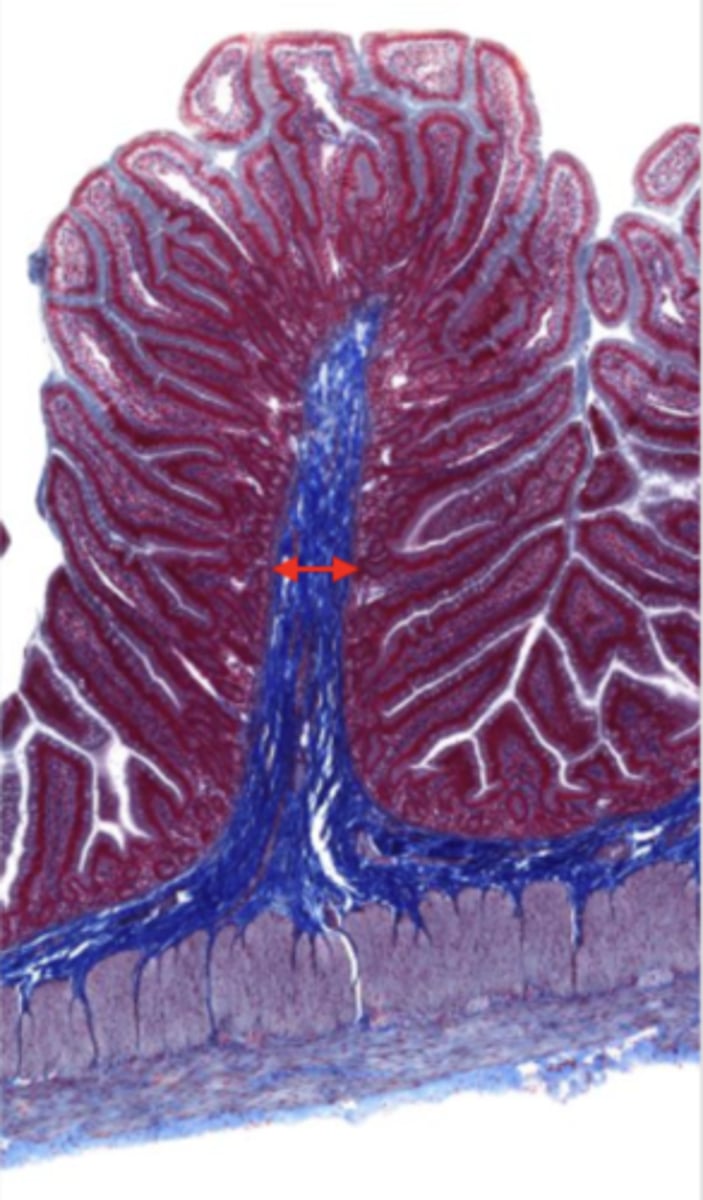

jejunum (histology)

simple columnar epithelium

villi (jejunum)

intestinal crypts (jejunum)

lumen (jejunum)

mucosa (jejunum)

mucosal epithelium (jejunum)

lamina propria (jejunum)

muscularis mucosa (jejunum)

submucosa (jejunum)

contains glands and blood supply

muscularis externa (jejunum)

serosa/adventitia (jejunum)